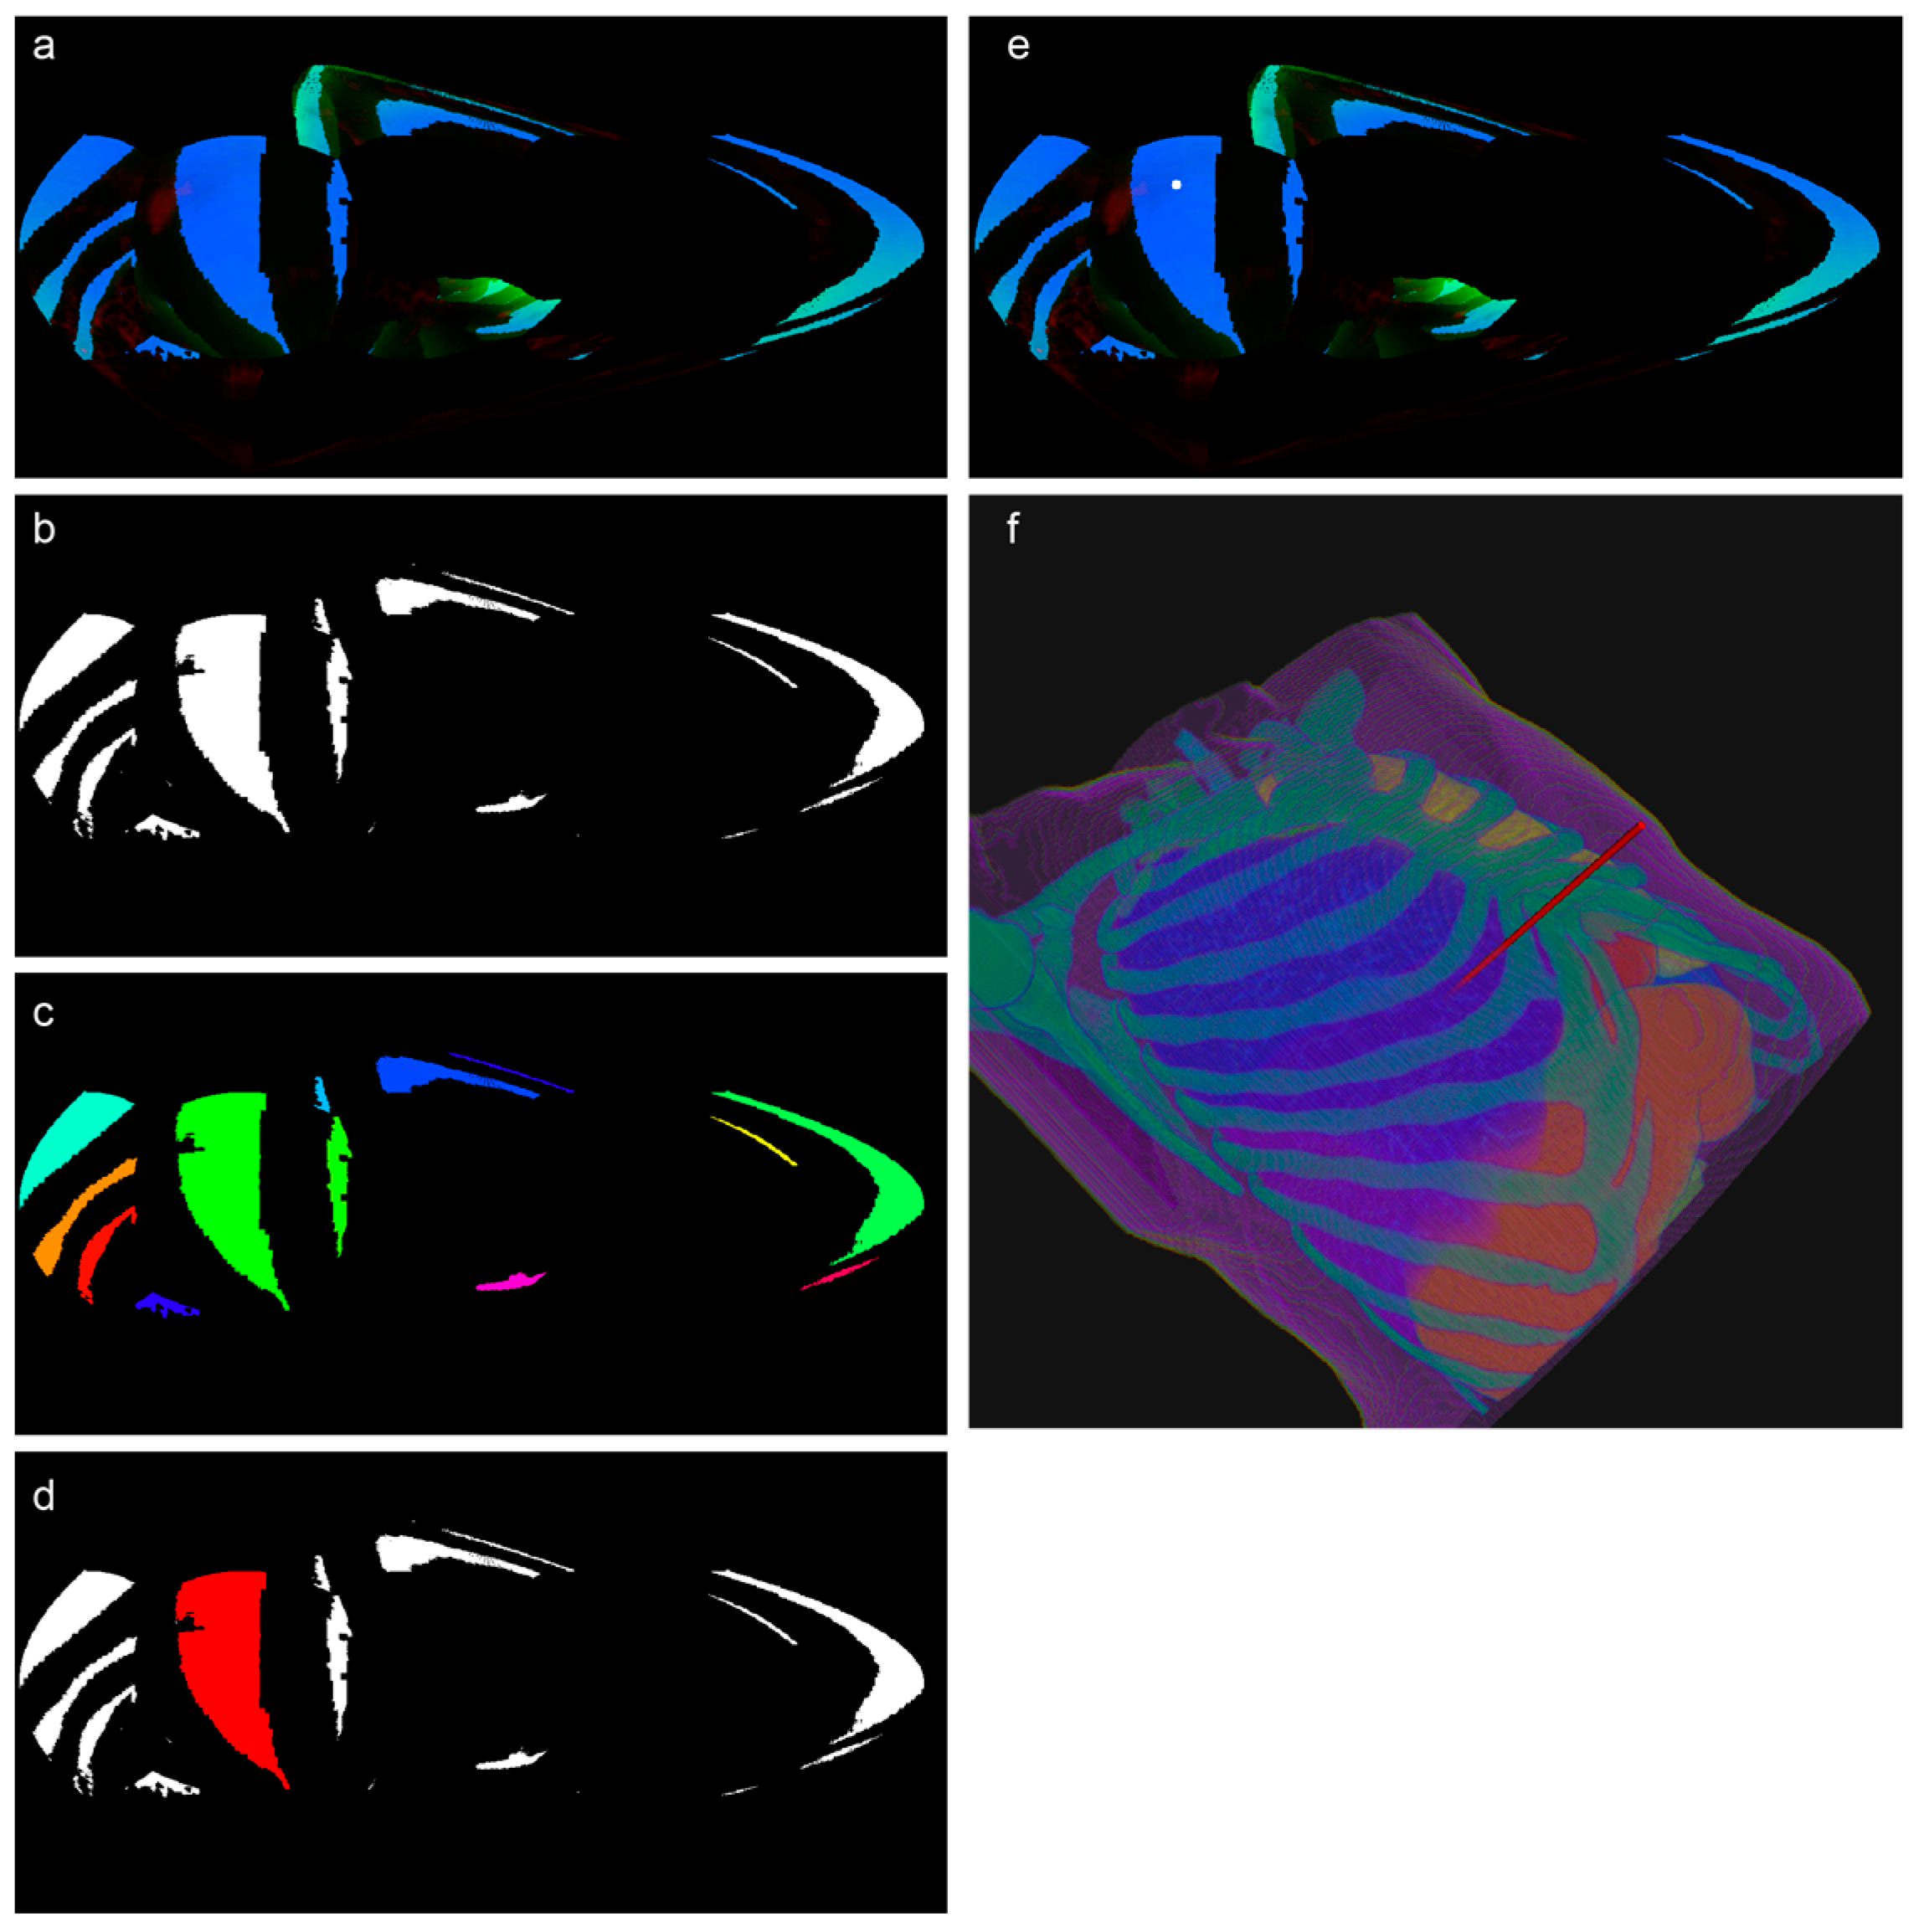

Figure 6a presents a 3D rendering of the organ and tissue segmentation masks for a sample case. To enhance visibility, the rendering excludes the skin and body tissues. Figure 6b is a magnified view of the target area with the target lung lobe hidden for clarity. The red arrow indicates the puncture target point. Figure 6c illustrates a typical result of the illumination intensity distribution described earlier. The human body mask appears spherical due to ROI cropping. Where the ROI intersects the CT image boundaries, the cuts are flat, and zero-padding is applied beyond these boundaries. The white image shows the light intensity distribution on the spherical screen, represented as a thin point cloud. Users can select an appropriate puncture entry point based on the light intensity distribution and the size of the illuminated regions. Figure 6d shows the result of mapping the selected puncture path back into 3D space. The red cylinder represents the simulated puncture needle path.

Figure 6.

Visualization of segmentation masks, illumination intensity distribution, and puncture path mapping. (a) Three-dimensional rendering of organ and tissue segmentation masks, with skin and body tissues hidden for clarity. (b) Magnified view of the puncture target area with the target lung lobe hidden. The red arrow indicates the puncture target point. (c) Typical illumination intensity distribution result. The human body mask is spherical due to ROI cropping, with flat cuts and zero-padding beyond the CT image boundaries. The spherical screen displays the light intensity distribution as a thin point cloud, enabling the selection of the optimal puncture entry point. (d) Three-dimensional mapping of the selected puncture path. The red cylinder represents the simulated puncture needle path.

The sinusoidal projection, an equal-area projection method, preserves the relative area sizes and provides an intuitive visualization of the feasible puncture regions. As CT scanning beds are typically positioned below the patient, we chose the ventral side (anterior) of the ROI as the projection center. The RGB channels were combined into a single image, as shown in Figure 7a.

Figure 7.

From illumination map to puncture path: visual biopsy trajectory planning. (a) RGB Sinusoidal Projection: Illumination results (attenuation terms and obstacle indicator) mapped to RGB channels and projected onto a 2D planar image using sinusoidal projection, visualizing feasible puncture regions while preserving area ratios. In the RGB projection, the blue, red, and green channels, respectively, represent the intensity parameters for ‘ref’, ‘vas’, and ‘trans’ terms. (b) Initial Region Segmentation: Low-risk regions are segmented by applying statistical thresholds to the RGB values, determining the RGB value ranges for safe regions based on the statistical distribution of the RGB channels, thus identifying potential areas of interest. (c) Filtered Safe Regions: Filtered safe regions were obtained after setting a size threshold based on clinical experience to remove smaller candidate regions. (d) Expert Annotation: Expert annotation by a thoracic surgeon who selected a recommended needle insertion region based on their clinical experience. (e) Final Puncture Point: Final puncture point determined by expert annotation or machine learning prediction and refined to a single pixel via iterative erosion (indicated by a white dot). (f) Biopsy Trajectory: 2D puncture point reverse-mapped to 3D CT space, visualizing the calculated biopsy needle trajectory (red cylinder).

The segmentation of low-risk regions was guided by the statistical distribution of the RGB values across the dataset. Thresholds were applied to the RGB channels to identify the regions of interest, effectively dividing the images into distinct segments. Using these thresholds, safe regions were extracted, segmented into discrete connected components, and filtered to exclude small regions below a set size threshold (Figure 7b,c).

To incorporate clinical expertise, an experienced thoracic surgeon reviewed the segmented regions and annotated the preferred puncture points on the projected images (Figure 7d).

The final puncture point was determined based on either the annotations of the surgeon or the predictions of the machine learning model. For the selected target region, iterative erosion was applied until a single pixel remained, representing the puncture point (indicated as a white dot in Figure 7e). This 2D point was then reverse-mapped to the original 3D space to calculate the biopsy trajectory (Figure 7f, where the red cylinder represents the needle path).